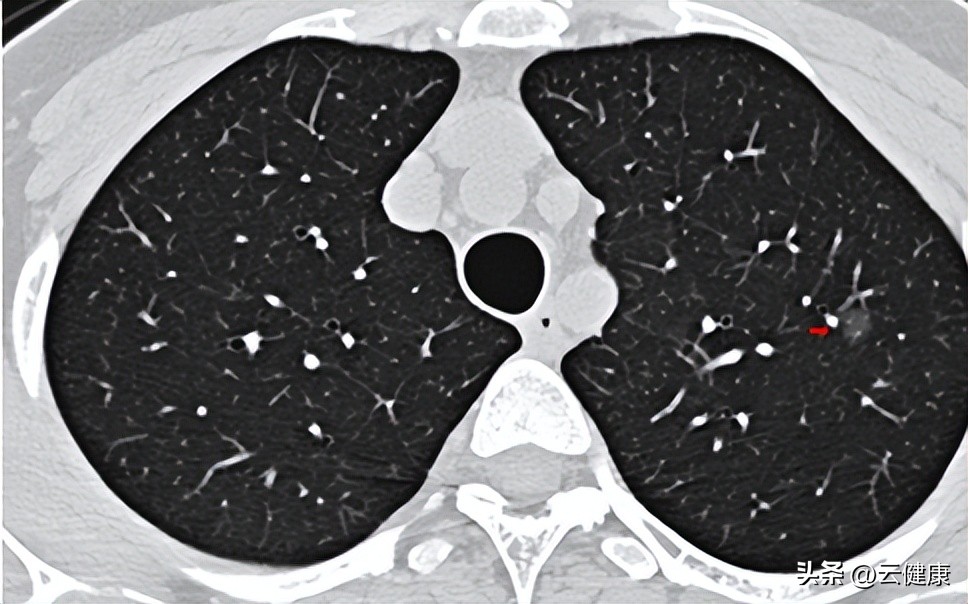

当我们的肺部出现健康问题时,比如出现一些危害健康的疾病,如肺气肿、肺炎、气管炎以及肺结节等,会导致肺泡的弹性降低,进而影响呼吸能力,所以日常生活中需要特别注意此外,肺作为呼吸器官,每天都有很多的粉尘颗粒物和微小生物体等通过呼吸沉积在肺内,肺很容易长出结节样的东西还真是不奇怪,还有各种感染性的疾病也会形成结节样改变。